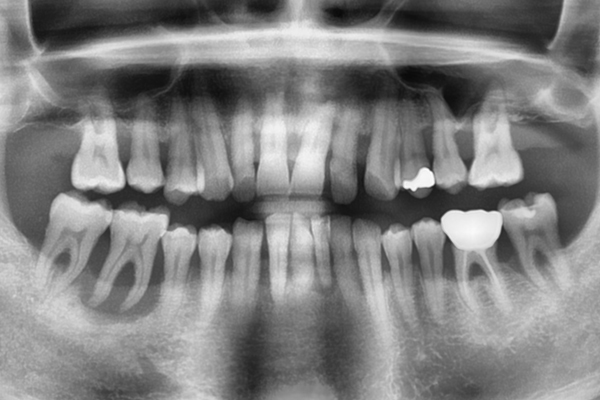

임플란트 시술은 환자분의 잇몸 뼈와 주변 구조물의

상태에 따라 다양한 방법으로 시행됩니다. 만약 임플란트를 시술할

잇몸 뼈나 주변상태가 좋지 않은 경우 임플란트 시술은

더욱 난이도 높은 수술 방법을 필요로 합니다.